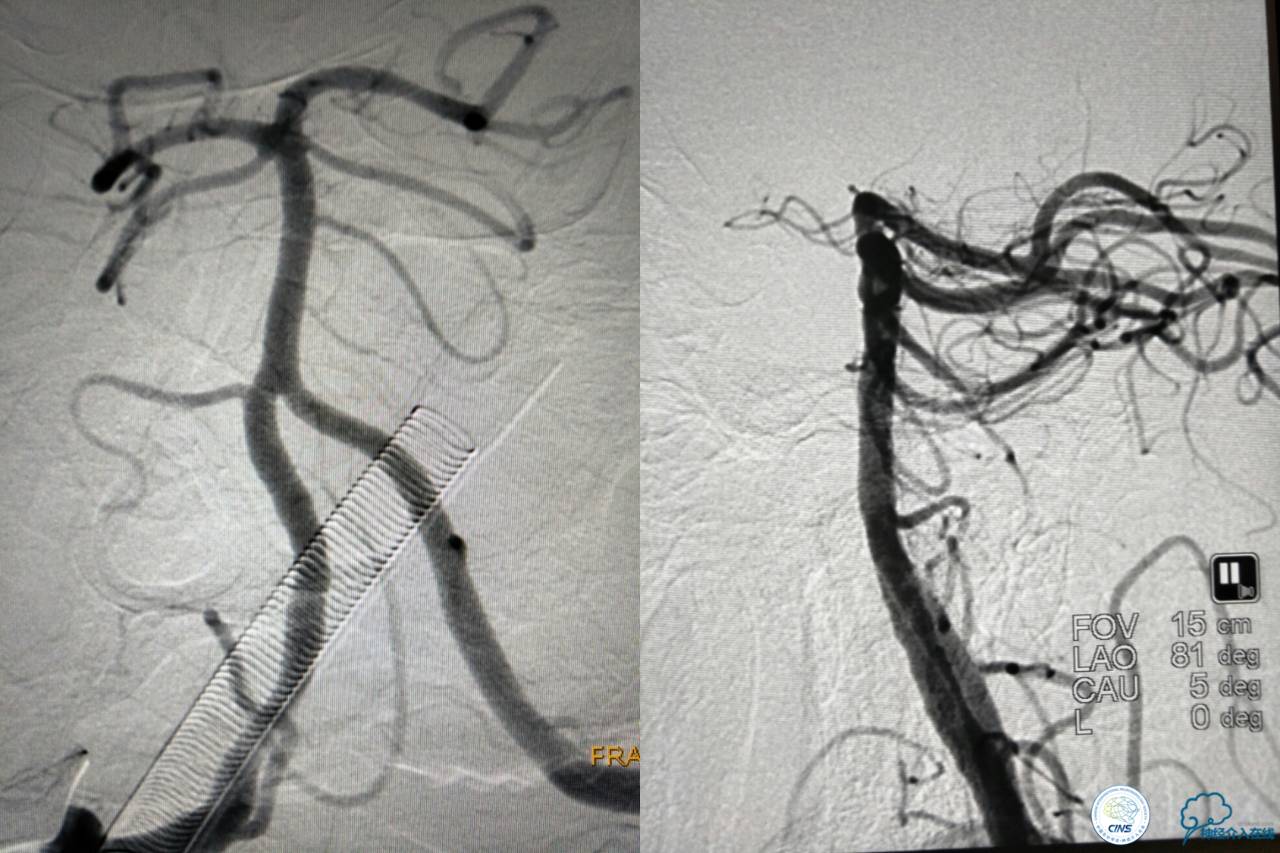

血栓负荷还是很大,左侧大脑后再通,但右侧大脑后又闭塞,只能第五次取栓,支架放到右侧大脑后动脉更远。

好大的血栓,支架释放后,血管无复流,拉一把!

没错,没看错!血管成功实现再通,术中取栓的栓子如下。

术后

术后生命体征平稳,成功撤呼吸机,肌力较前好转,复查头颅CT:

右侧丘脑高密度影,右侧枕叶可能也有梗死,祈祷慢慢恢复吧!